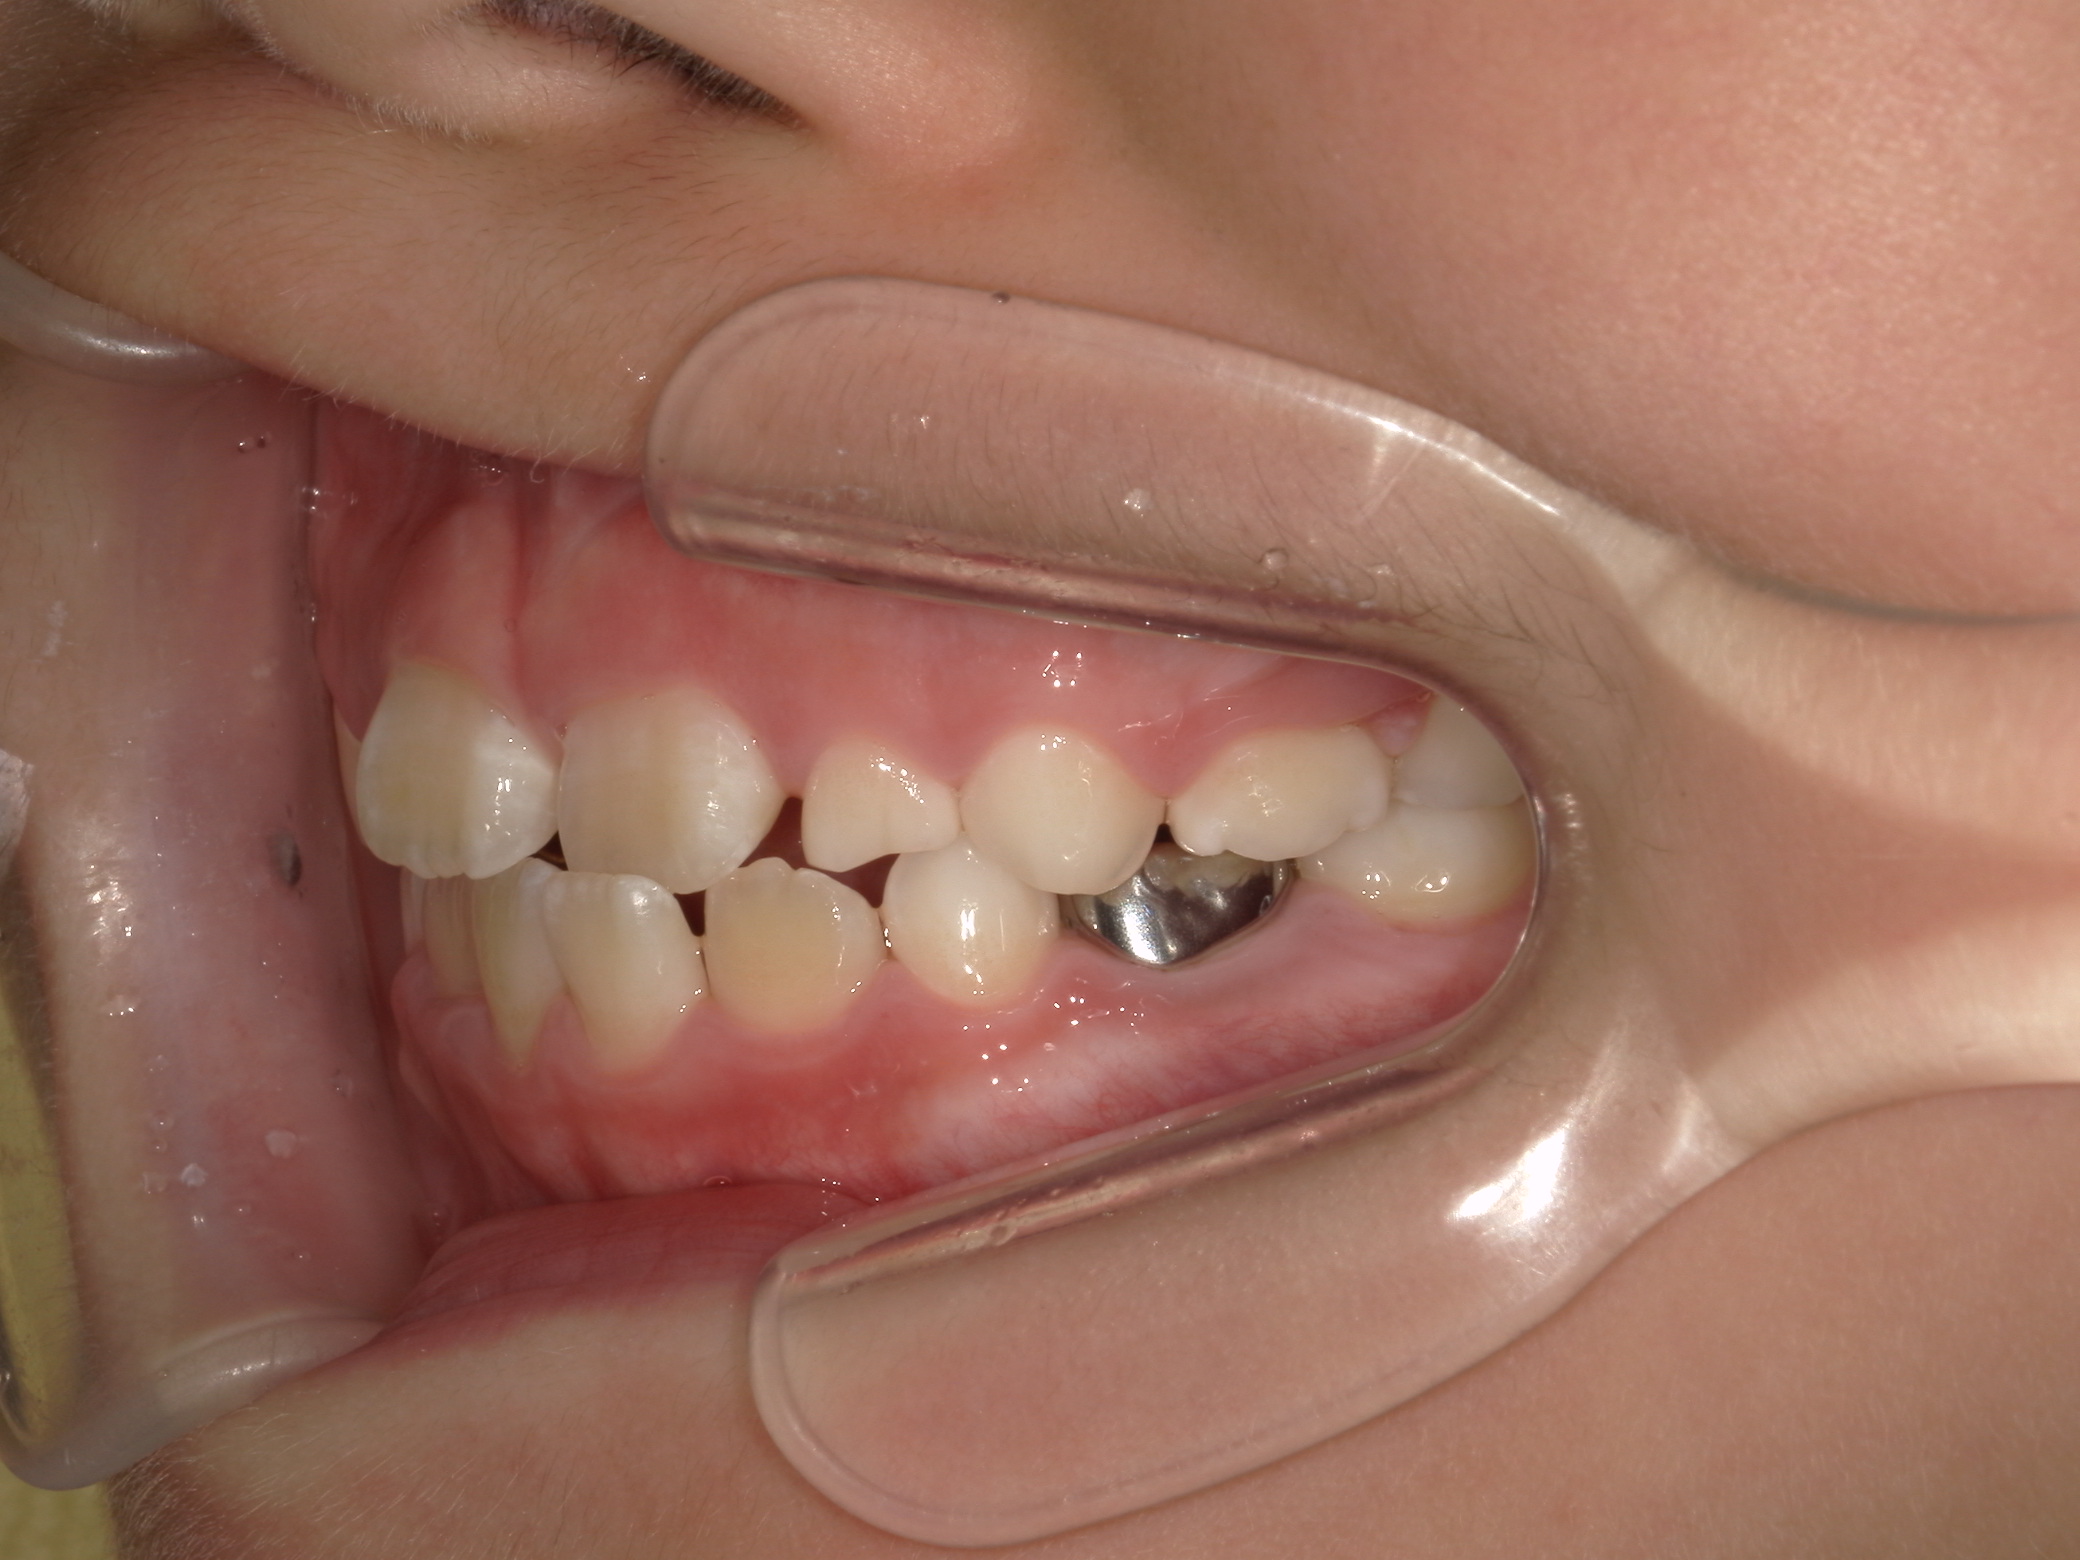

【小学生】マイオブレース矯正 反対咬合(受け口)を改善

小学生で開始

マイオブレース

受け口

非抜歯

1期治療のみで改善

Before

After

治療期間

1.6年

治療開始

8歳

種類

マイオブレース矯正

使用装置

機能矯正装置

コメント

装置装着と 筋機能療法をきっちり取り組んでくれましたので

スムーズに治りました。

現在も安定して 後戻りしていません。